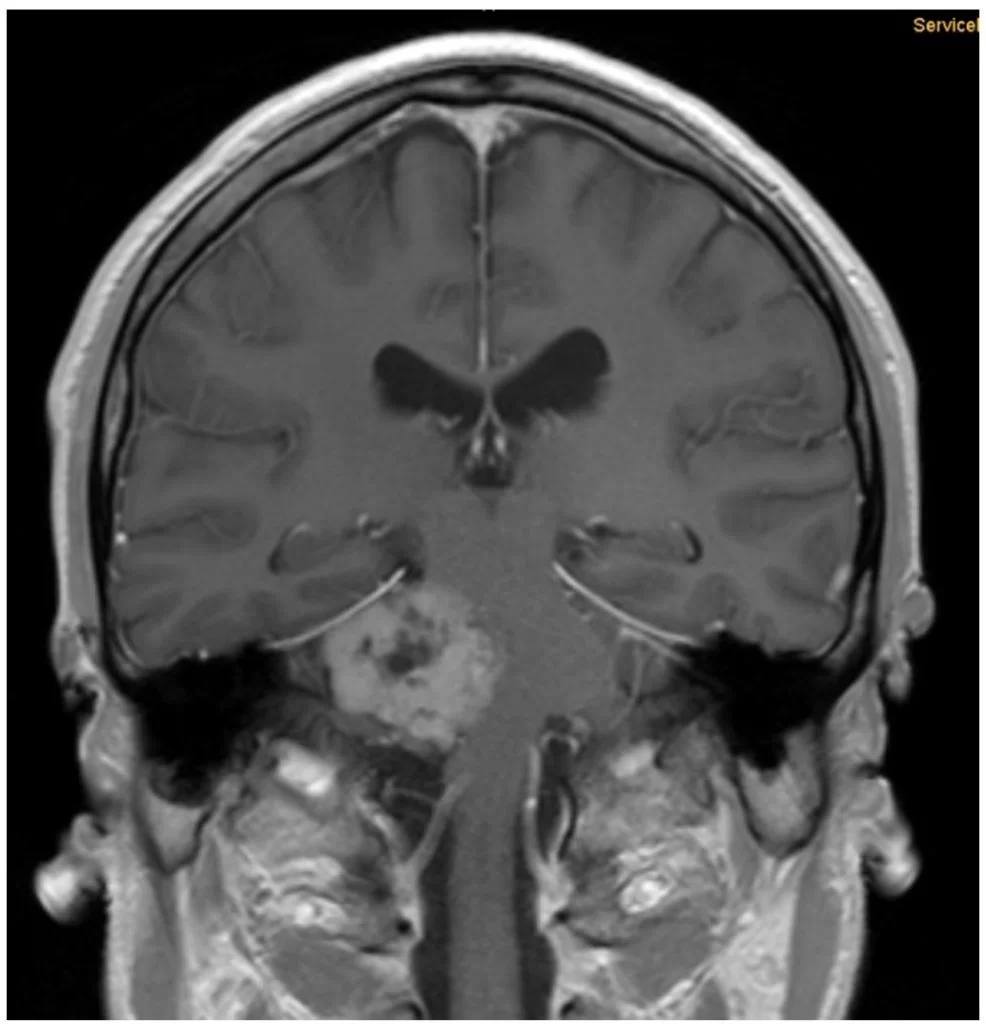

Η μαγνητική τομογραφία εγκεφάλου ανέδειξε εκτεταμένη χωροκατακτητική εξεργασία στην γεφυροπαρεγκεφαλιδική γωνία δεξιά, με επέκταση στην περιοχή του γασσέρειου γαγγλίου του τριδύμου .

Διενεργήθη δεξιά οπισθοσιγμοειδική κρανιοτομία με drilling της κορυφής του λιθοειδούς (suprameatal apicectomy)

Η μετεγχειρητική μαγνητική τομογραφία εγκεφάλου δείχνει ένα εξαιρετικό αποτέλεσμα, με πλήρη αφαίρεση της βλάβης. Η ιστολογική ανέδειξε μηνιγγίωμα WHO I.